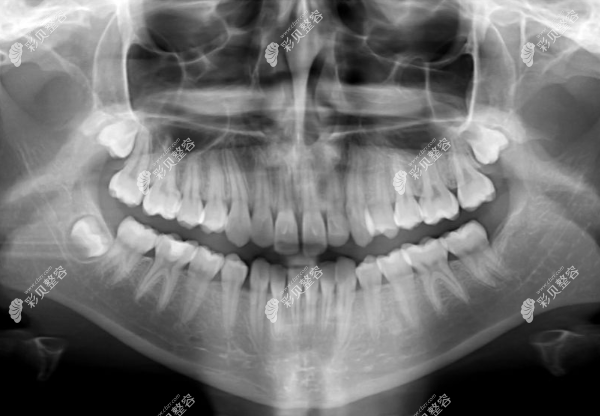

1、术前拍摄X线片

帮助医生能直观看到顾客牙髓情况,判断牙髓髓室的位置和根管数目及形态,测量根管长度。

就像骨折拍的X光一样,方便医生判断,好针对性的做治疗方案。